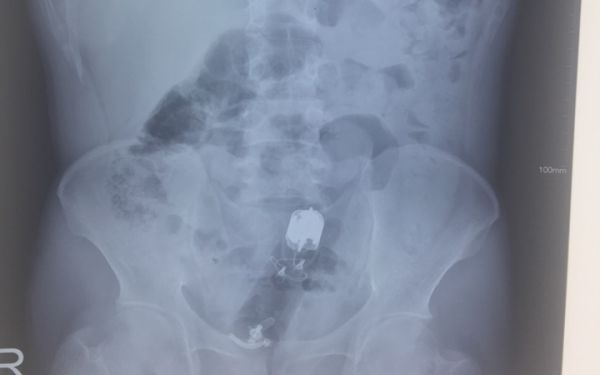

Sau khi kiểm tra, bác sĩ có thể yêu cầu chụp X-quang bụng để xem chính xác vị trí của dị vật. Nếu bạn bị đau bụng, chảy máu hoặc sốt, bạn sẽ được tiêm tĩnh mạch và làm xét nghiệm máu.